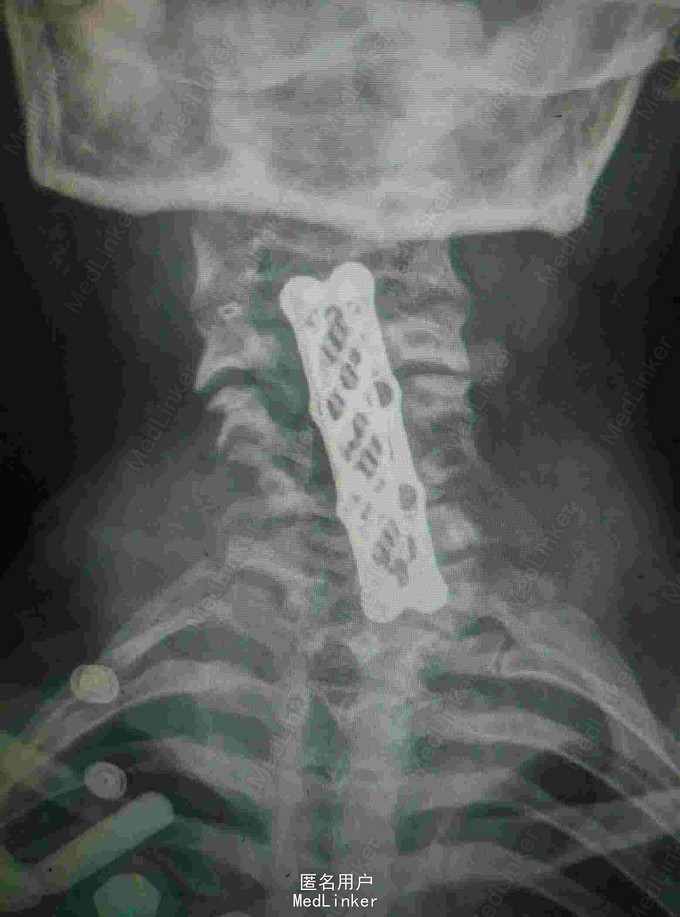

颈肩痛伴左侧肢体无力5月 患者青年男性,无明显诱因出现颈肩痛,性质钝痛,伴有左侧肢体无力,症状反复发作五月。于当地医院就诊查核磁提示颈椎结核,椎旁脓肿。患者二便正常,既往结核病史。

查体:颈椎生理弯曲消失,各棘突及椎旁压痛,胸腰椎生理弯曲不在,各棘突无压痛,椎旁无叩击痛。左侧肢体肌力降低,双侧Hoffoman征阳性,Babinski征阳性。 辅查:我院磁共振提示颈椎结核并椎旁脓肿,颈椎失稳。

诊断:颈椎结核伴椎旁脓肿 颈椎不稳 四肢不全瘫。 治疗:颈前路病灶清除植骨融合内固定术+Halos架固定,术后护肝抗结核治疗